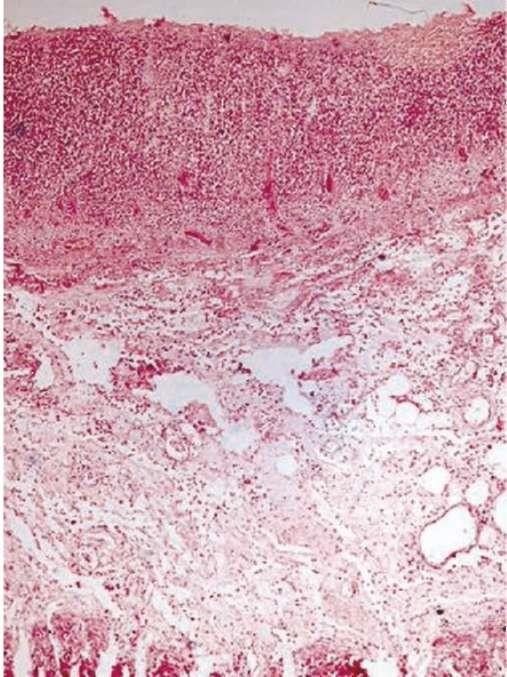

Флегмона - гнойное диффузное воспаление с пропитыванием и расслаиванием тканей гнойным экссудатом. Образование флегмоны зависит от патогенности возбудителя, состояния защитных систем организма, структурных особенностей тканей, где возникла флегмона и где есть условия для распространения гноя. Флегмона обычно возникает в подкожно-жировой клетчатке, межмышечных прослойках, стенке аппендикса, мозговых оболочках и т.п. (рис. 4.5). Флегмону волокнисто-жировой клетчатки называют целлюлитом.

Исходы. Заживление флегмонозного воспаления начинается с его отграничения с образованием грубого рубца. Обычно флегмону удаляют хирургическим путем с последующим рубцеванием операционной раны. При неблагоприятном исходе возможна генерализация инфекции и развитие сепсиса.